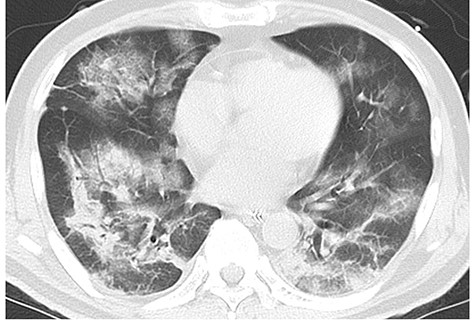

A 59-year-old man with a history of hypertension, type II diabetes mellitus, old myocardial infarction and chronic heart failure suffered from COVID-19 pneumonia 8 months prior to admission (Fig. 1). He required an artificial respirator on the ninth day of onset due to worsening of respiratory status. He underwent tracheotomy on the 19th day of onset. Two COVID-19 polymerase chain reaction (PCR) tests conducted on the 32nd day after the initial infection showed negative results. He was discharged on the 52nd day of onset. Six months after discharge, he presented with sudden abdominal pain and was admitted to our hospital. His vital signs were temperature, 35.1°C; heart rate, 74 beats per minute; blood pressure, 121/92 mmHg; and SpO2, 100% on room air. Physical examination showed board-like rigidity and rebound tenderness over the entire abdomen. Laboratory results showed significant increase in inflammatory response, with a white blood cell count of 18 000/μl. Computed tomography (CT) revealed ascites, free air in the abdominal cavity, multiple diverticula of the descending colon (Fig. 2b) and increased fat density surrounding the descending colon (Fig. 2c). We diagnosed the patient with colonic perforation and performed emergency surgery. Surgical findings revealed pinhole perforation in the descending colon (Fig. 3). As the perforation was small and there was no fragility of the surrounding colonic tissue, the perforation was sutured and closed. Then, the sutured site was covered with epiploicea appendices. A drain was placed in the left paracolic gutter after abdominal cleaning. The abdominal wall was closed without a diverting stoma. The patient was wheezing on the first postoperative day, and he required oxygenation when SpO2 dropped to 70% on room air. His COVID-19 PCR test was negative. The cardiothoracic ratio, which was 40% preoperatively, increased to 50%. He was diagnosed with exacerbation of chronic heart failure and was treated with diuretics, and his symptoms improved. He passed without any complications, and he was discharged from the hospital 13 days after the operation.

Chest CT at the onset of COVID-19 showing bilateral patchy ground-glass opacities and infiltrative shadows.